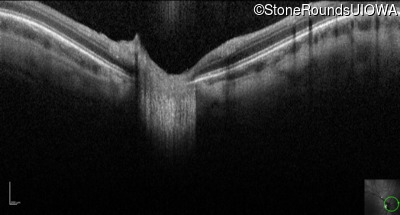

Optical Coherence Tomography - Right - 10/160 sc

Exemplar

Optical Coherence Tomography - Left - 10/200 sc

Exemplar / OCT Stack